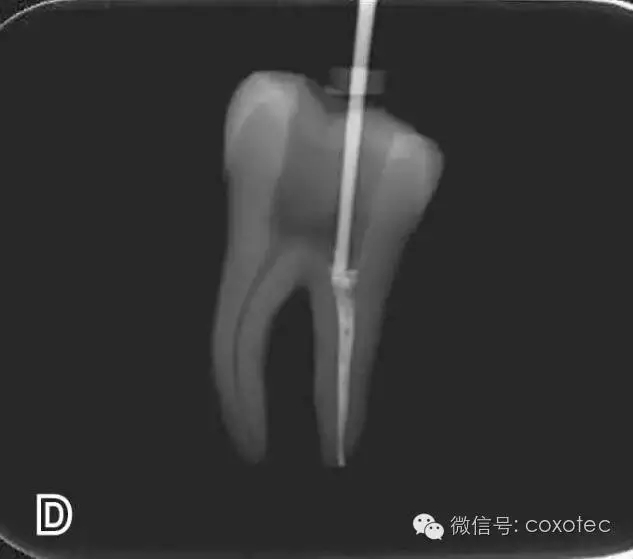

選擇非標(biāo)準(zhǔn)牙膠尖(如0.04、0.06 錐度牙膠尖)作為主尖,型號(hào)一般與根管預(yù)備最大號(hào)的器械型號(hào)一致,能到達(dá)距根尖0.5~1 mm 處,主尖尖段與根管壁緊密接觸。拍試尖X 線片進(jìn)行確認(rèn)(圖3)。

圖3 試尖,A.試主尖 B.拍試尖X片